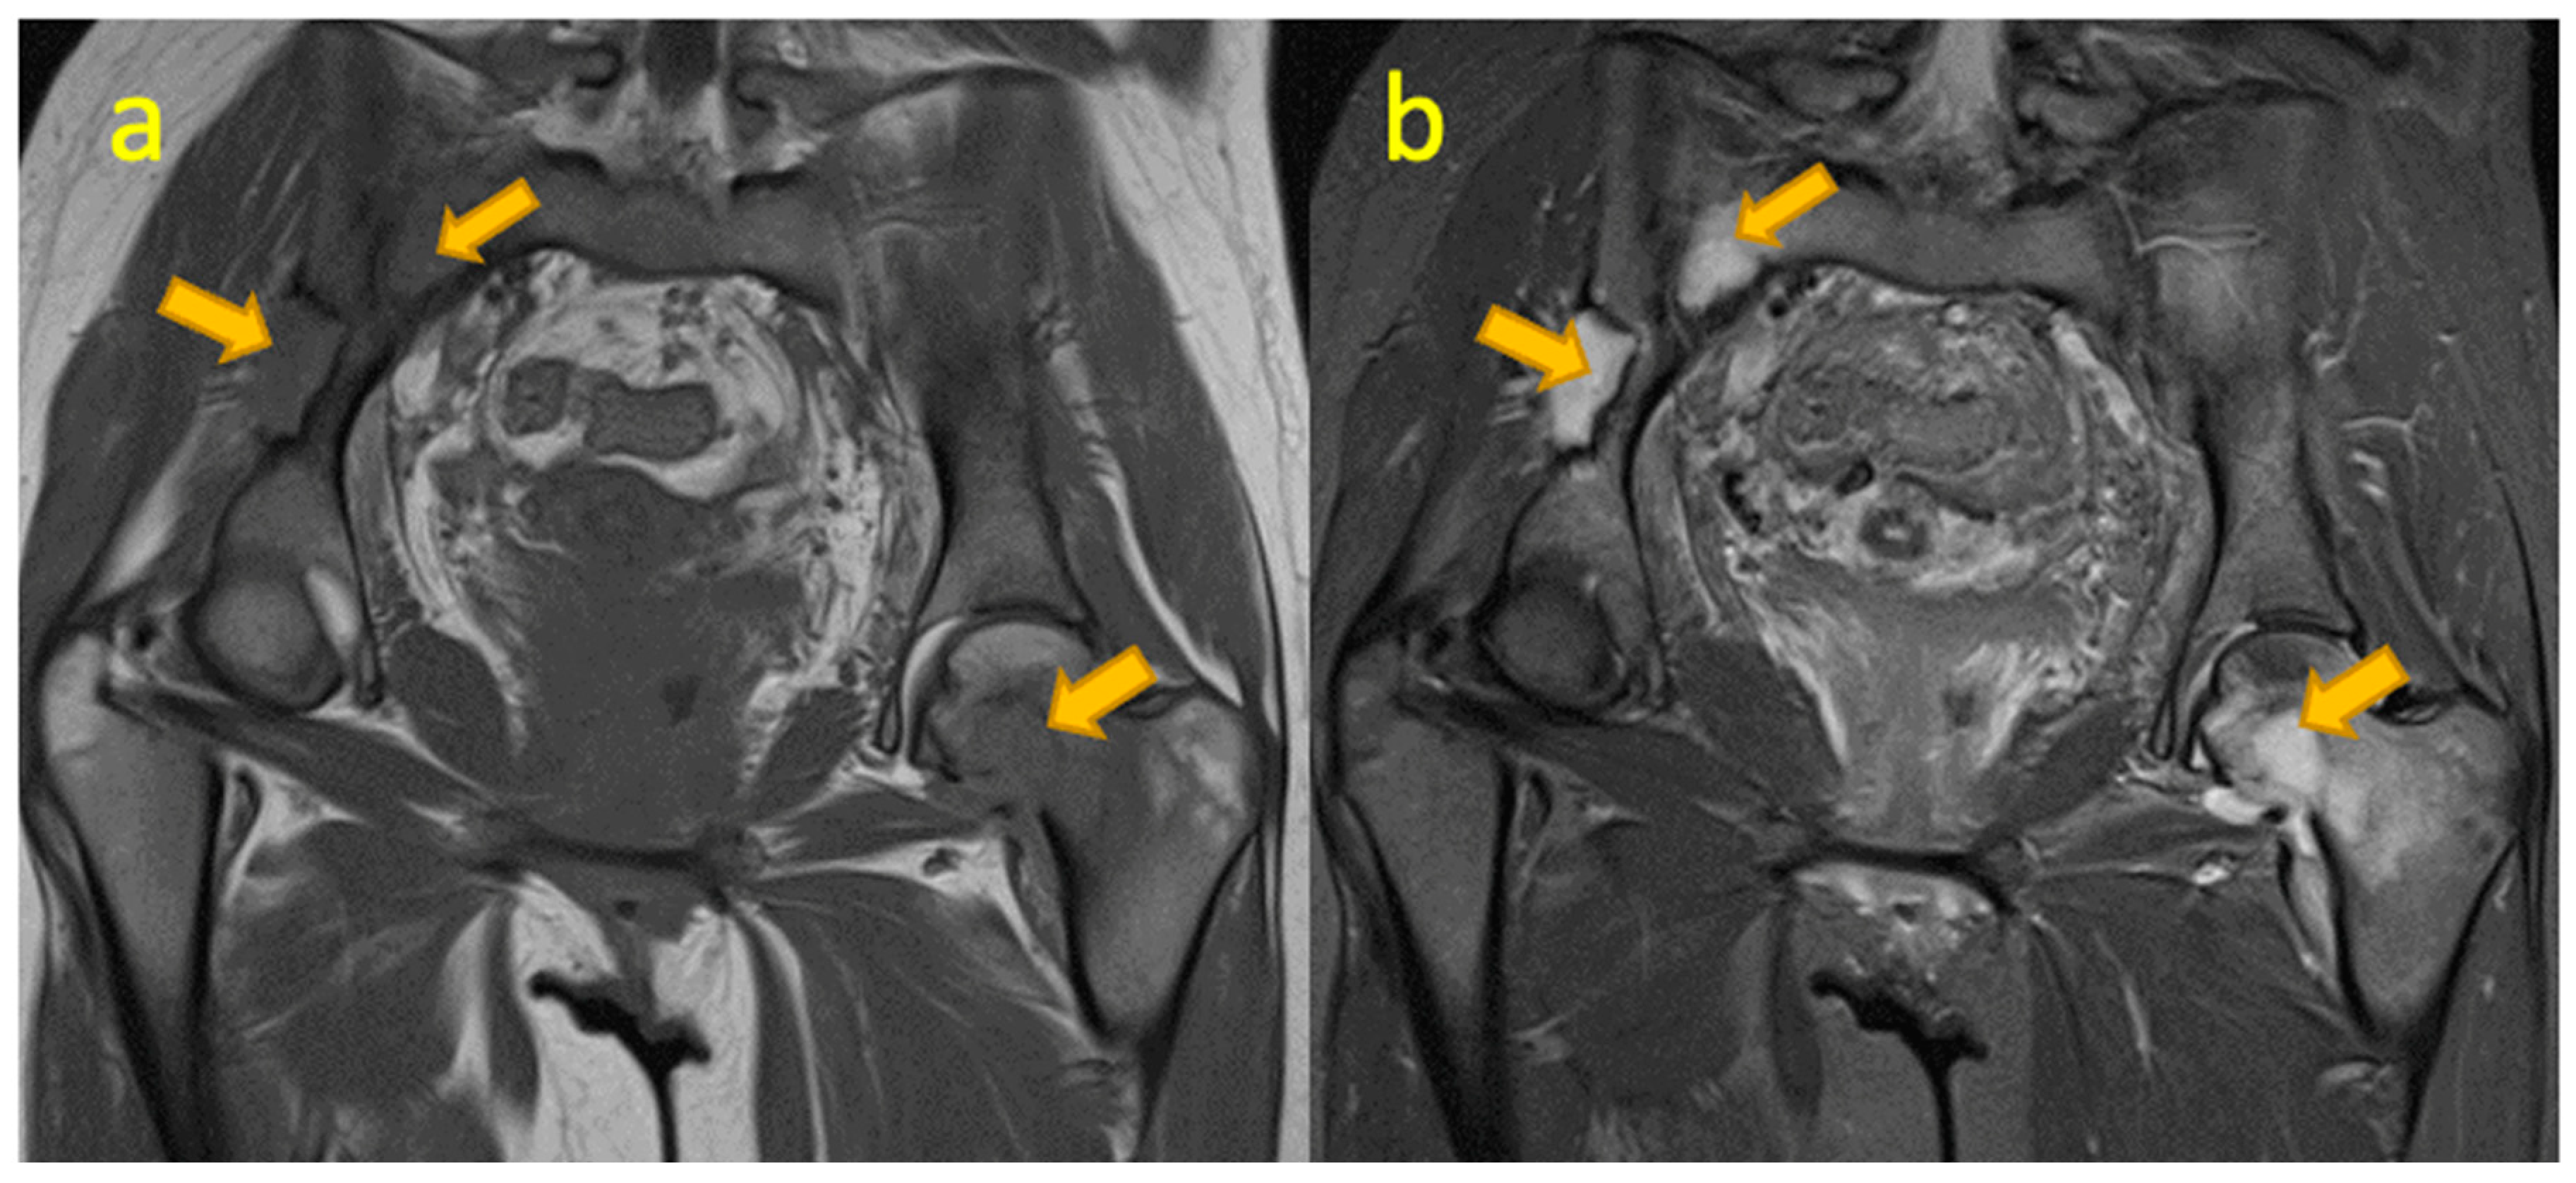

13. Septic Arthritis of the Sacroiliac Joint

- Lavi, E.; Gileles-Hillel, A.; Simanovsky, N.; Averbuch, D.; Wexler, I.D.; Berkun, Y. Pyogenic sacroiliitis in children: Don’t forget the very young. Eur. J. Pediatr. 2019, 178, 575–579. [Google Scholar] [CrossRef] [PubMed]

- Schaad, U.B.; McCracken, G.H.; Nelson, J.D. Pyogenic arthritis of the sacroiliac joint in pediatric patients. Pediatrics 1980, 66, 375–379. [Google Scholar] [CrossRef]

- Wada, A.; Takamura, K.; Fujii, T.; Yanagida, H.; Surijamorn, P. Septic sacroiliitis in children. J. Pediatr. Orthop. 2008, 28, 488–492. [Google Scholar] [CrossRef] [PubMed]